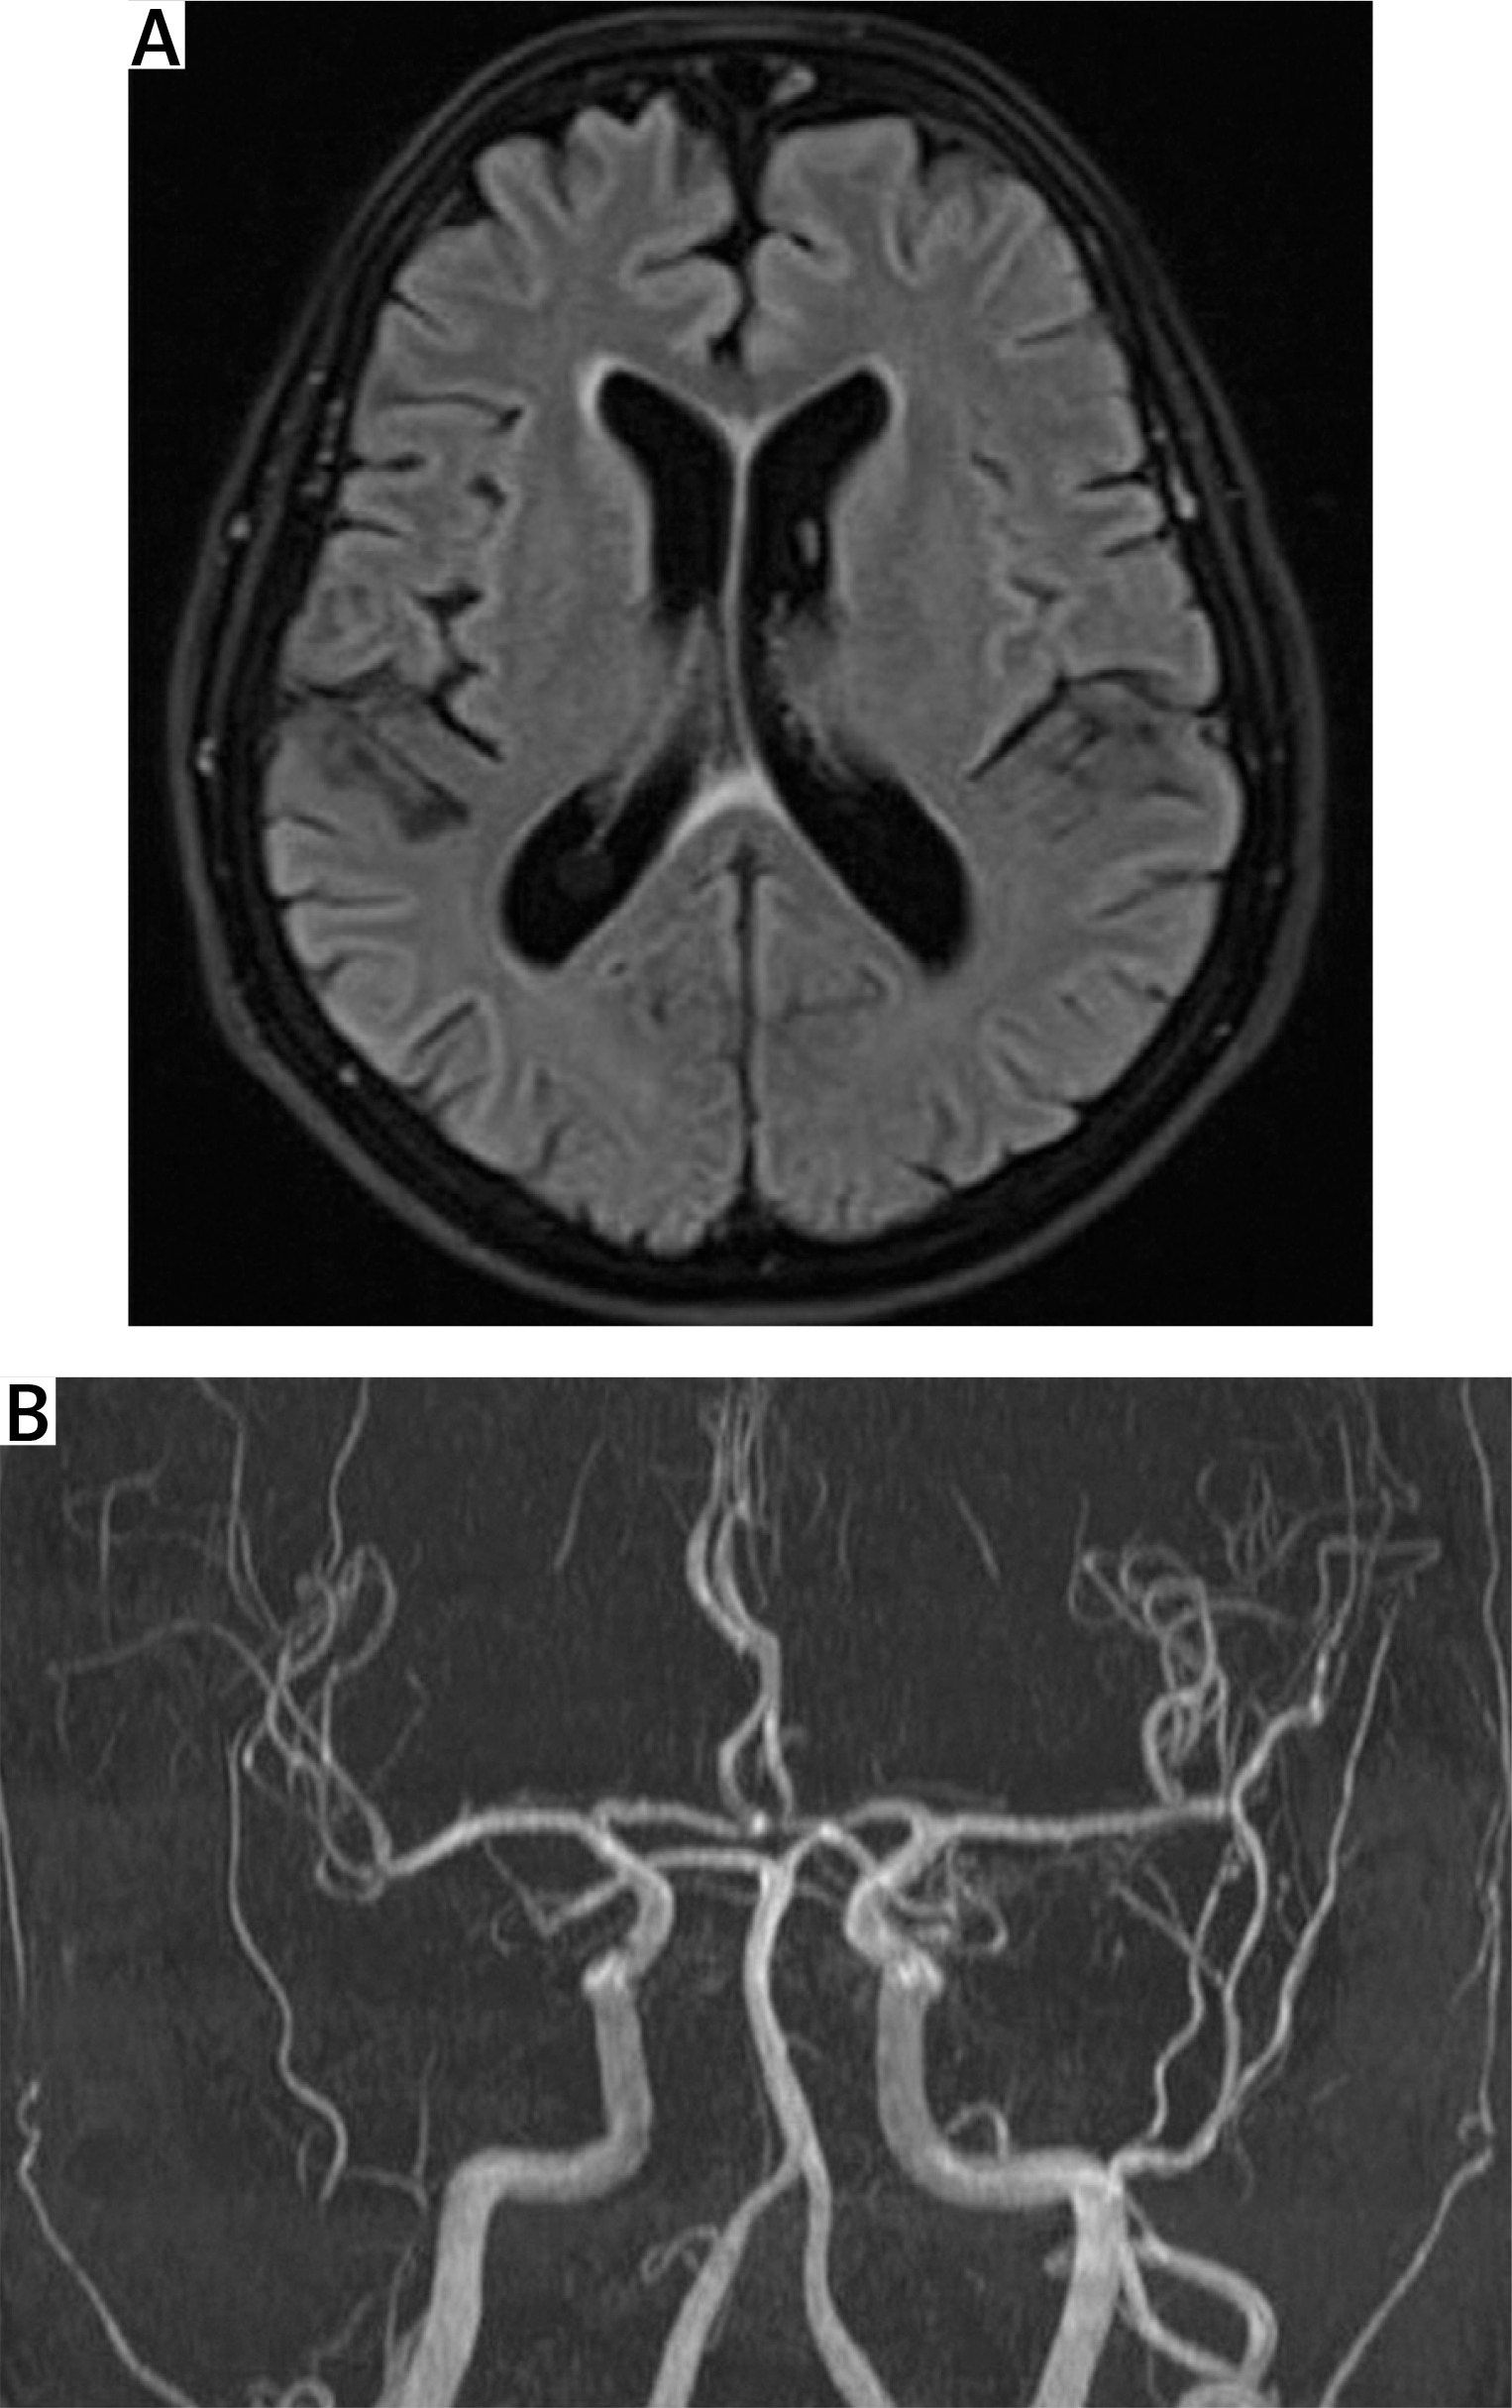

Head magnetic resonance angiography (MRA) and venography with contrast were within normal limits (Fig. 2). Erythrocyte sedimentation rate and CRP levels were normal. The halo sign on both temporal and axillary artery ultrasound was absent. The Southend Giant Cell Arteritis Probability Score (GCAPS) score was 15 [1].